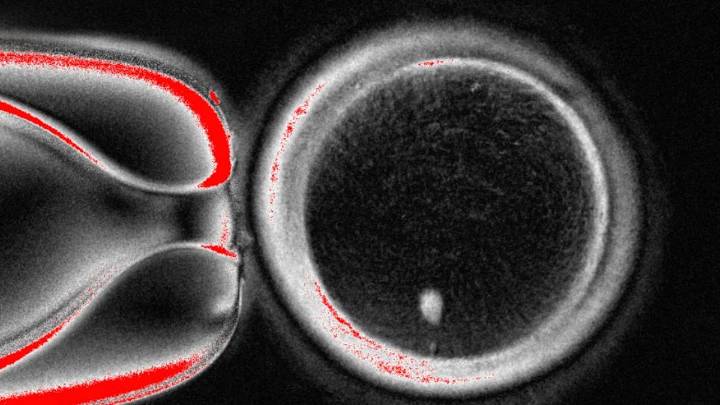

Foto sin fecha, suministrada por el Laboratorio Mitalipov Laboratory en la Universidad de Salud y Ciencia de Oregon, que muestra una imagen microscópica de un óvulo humano que contiene un núcleo tomado de una célula de piel. (Laboratorio Mitalipov via AP) Mitalipov Laboratory at Oregon Health & Science University

Sin embargo, el experimento resultó en anomalías en los cromosomas, lo que llevó al equipo de la Universidad de Salud y Ciencia de Oregon (o Oregon Health & Science University, OHSU) a advertir que podría tomar una década de investigación adicional antes de que tal técnica esté lista para ensayos en personas.

El trabajo publicado el martes en Nature Communications puede ofrecer lecciones mientras los científicos intentan aprender a crear óvulos y espermatozoides en un laborator